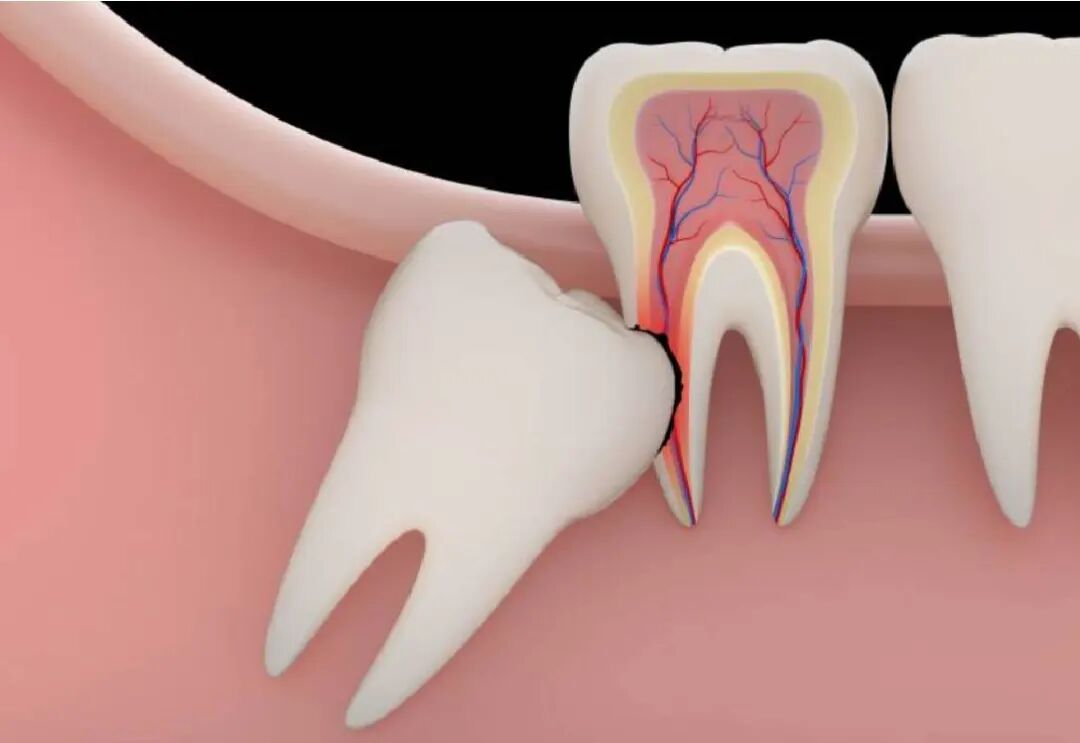

4)侵犯邻牙:邻牙不易清洁,容易龋坏/压迫牙根,引起牙根吸收